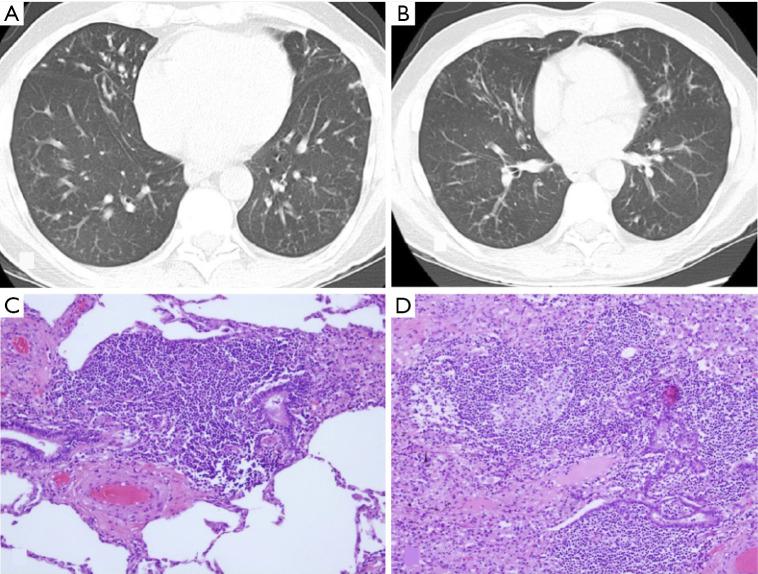

BACKGROUND AND OBJECTIVE

Interstitial lung diseases (ILDs) encompass over 200 entities. Among them, fibrosing lung diseases, have recently generated special interest due to the emerging therapies for their management. However, it is important to deepen our knowledge of other less prevalent ILD, since many of them are associated with a poor prognosis. This narrative review aims to provide a practical and up-to-date description of some poorly recognized ILD. It covers rare idiopathic interstitial pneumonias and their histologic patterns, genetic disorders with interstitial lung involvement (Hermansky-Pudlak syndrome), and ILD associated with benign proliferation of pulmonary lymphoid tissue, namely follicular bronchiolitis and granulomatous-lymphocytic interstitial lung disease.

KEY CONTENT AND FINDINGS

Despite the low prevalence of these diseases, the increased recognition of radiological patterns, pathological features, and diagnostic procedures, have permitted their better characterization. This review highlights epidemiology, clinical presentation, diagnosis, natural history, and treatment.